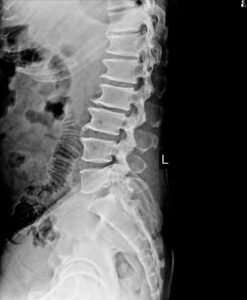

Как изглеждат остеофити на рентген или MRI

Остеофитите най-често се установяват чрез образни изследвания като рентгенография или MRI. Тези изследвания позволяват да се видят костните структури и промените в гръбначния стълб.

При образни изследвания могат да се наблюдават:

-

костни израстъци по краищата на прешлените

дегенеративни промени в ставите

намалена височина на междупрешленните дискове

стеснение на пространството около нервните структури

Образните изследвания дават ценна информация за структурата на гръбначния стълб, но винаги трябва да се разглеждат заедно със симптомите на пациента.